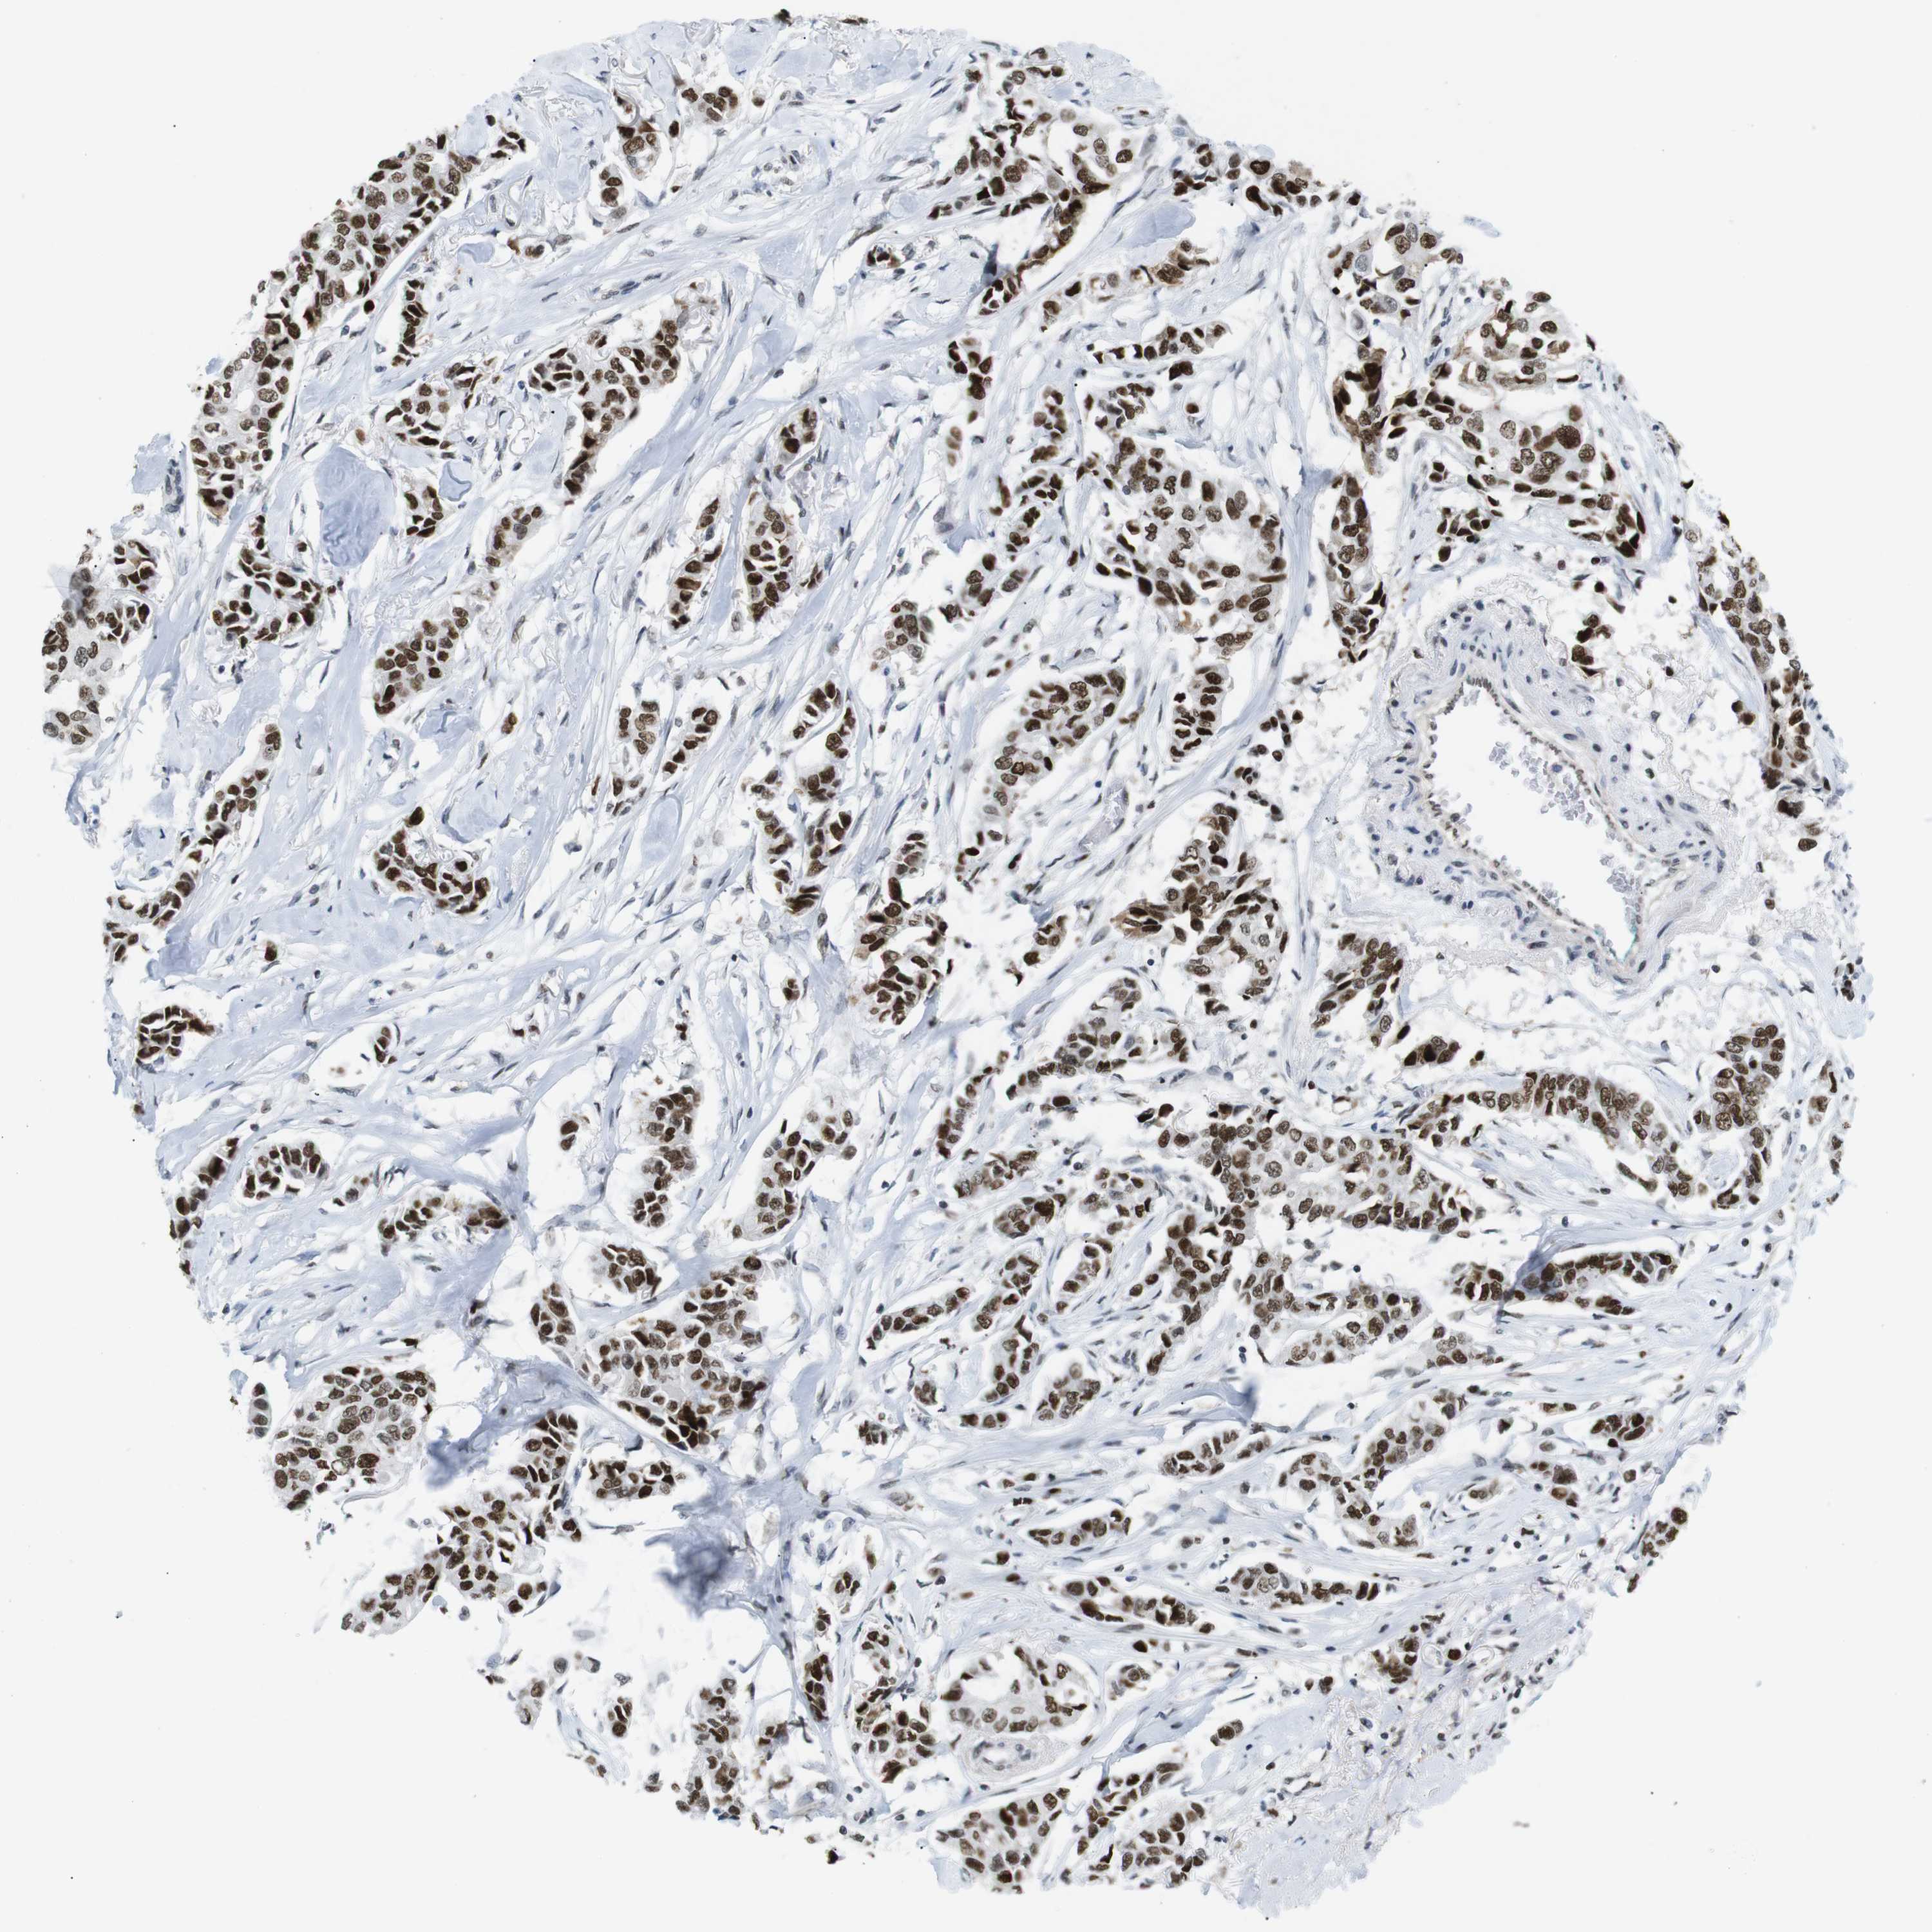

CANCER BREAST CANCER Show tissue menu

BRCA TCGA BRCA VALIDATION PROTEIN EXPRESSION

ANTIBODIES

AND

VALIDATION

RIOX2 is potential prognostic, high expression is unfavorable in Breast Invasive Carcinoma (TCGA)